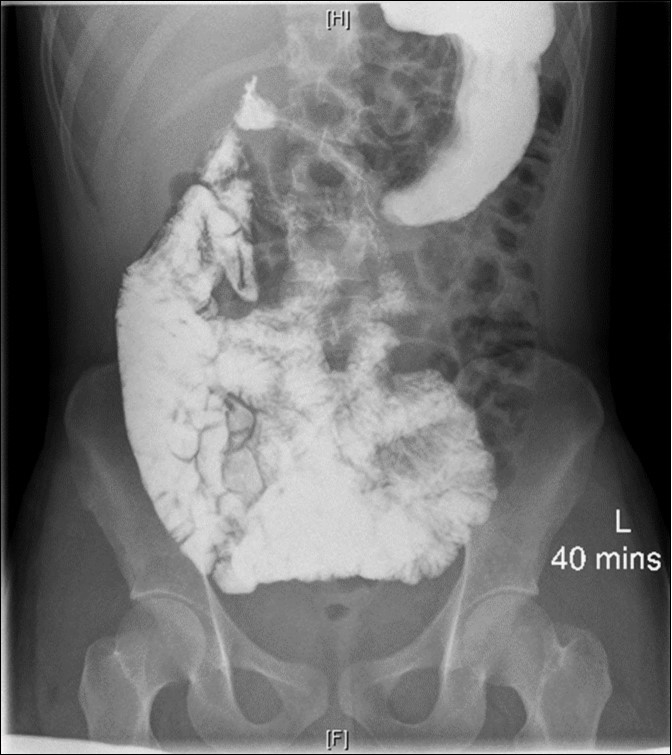

As part of the workup, an enterography magnetic resonance imaging (MRI) was done and showed non-rotation with the small bowel and colon in the right and left abdomen, respectively (Figure 1). A complementary upper gastrointestinal series (UGIS) was requested and the duodenal jejunal junction was abnormally located confirming malrotation (Figure 2).

Figure 2.UGIS showing malrotation